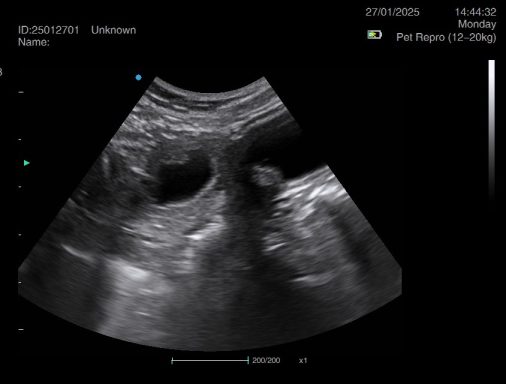

Ultrasound pregnancy scanning is a safe, non-invasive way to confirm pregnancy in dogs and cats, offering breeders and pet owners peace of mind and vital information to support responsible care. It allows us to detect gestational sacs, assess foetal development, and estimate litter size—all while ensuring the wellbeing of the animal.

Pregnancy can sometimes be detected as early as Day 18 post-mating, but scanning at this stage is not routinely recommended. Embryos are still developing and may not be clearly visible, and there is a natural risk of embryo resorption, which can lead to misleading or inconclusive results.

For the most accurate and reliable scan, we advise booking between Day 25 and Day 32, when pregnancy is more easily confirmed and foetal structures are clearer. If an early scan is performed and no pregnancy is detected, we offer a FREE complimentary re-scan after 7 days at the clinic to ensure clarity and support informed decision-making.